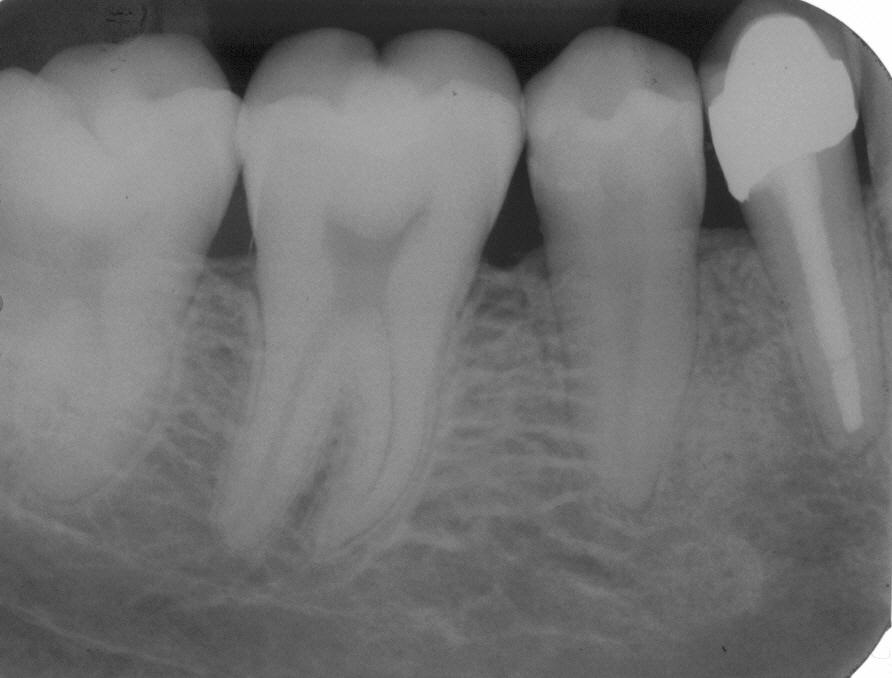

Röntgenologischer Ausgangsbefund im März 1996 bei Zahn 13 mit Silberstiftwurzelfüllung und chronisch apikaler Parodontitis; Zustand vor umfangreicher ZE-Neuversorgung. Erste Therapie der Wahl ist in diesem Fall immer die orthograde Revision

Wurzelfüllung im April 1996 in lateraler Kondensation mit normierter Guttapercha und AH 26